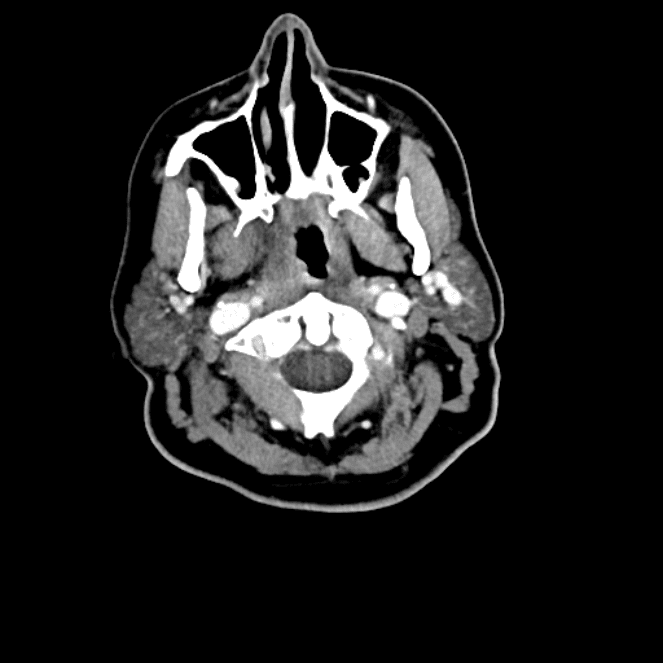

Head and Neck

Practice

Simulates call by including subtle or difficult cases and some normals.

27 cases